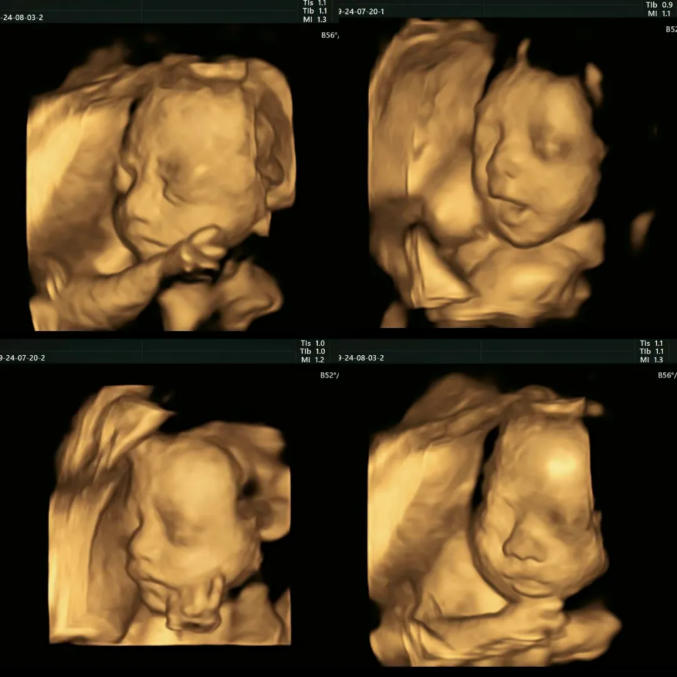

四维彩超的全称是四维彩色超声诊断仪,是现代先进的彩色超声设备。

四维彩超能够表面成像,更加清晰的筛查胎儿的四肢发育是否畸形,是否脑膜膨出,是否唇腭裂、是否脊柱裂等先天畸形,及早发现并及早做出解决方案。